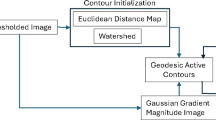

Anatomical sub-divisions for strain-time analyses

Unlike the LV, there is currently no standard method for dividing the RV into anatomical sub-regions. Previous studies of the RV using myocardial tagging have adopted different conventions for sub-dividing the RV. Klein et al. divides each RV basal, mid and apical short axis slice into three regions: superior, mid and inferior [18]. Haber et al. [4], divided the RV into four regions according to anatomical landmarks. The parietal and septal bands were used to demarcate the outflow region, while the free wall was identified based on the normalized height of the septum in a long axis view [4]. Fayad et al. divides the RV using the supraventricular crest (SC), moderator band, papillary muscles and the tricuspid valve as landmarks, creating four distinct regions: the inflow, outflow, mid and apical regions [19].

We propose dividing the RV surface in a similar manner to Fayad et al. These regions are illustrated in Figure 3. The divisions were defined by navigating through the 3D DENSE magnitude-reconstructed images and identifying three landmark coordinates as follows:

Right ventricular regional divisions. (a) Long axis view showing the level of the SC (top red dotted line) and moderator band (bottom red dotted line). (b) RV surface showing the four anatomical regions. (c, d) Short axis view corresponding to the partitions at the level of the SC and moderator band, respectively. The white and yellow arrows show the SC and moderator band, respectively.

Coordinate 1: The SC is an accentuation of the muscular wall demarcating the inflow and outflow tracts within the RV. Navigate from apex to base along the short axis magnitude images until the SC appears in the image. The first coordinate is marked on the RV free wall at the level of and adjacent to the SC.

Coordinates 2 and 3: The moderator band is a muscular band connecting the interventricular septum to the anterior papillary muscle of the tricuspid valve. Navigate from base to apex along the short axis magnitude images and define the slice where the moderator band becomes evident as a segment of myocardium crossing the RV cavity. The second and third coordinates are defined as the anterior and inferior RV-LV insertion points at this level, respectively.

The apical RV region is defined as the myocardium lying apical to the slice identified by the moderator band. The inflow, mid and outflow RV regions are defined using two planes: (i) a plane defined by coordinate 1, coordinate 2 and a point displaced normal to the RV mid-line surface in this region, and (ii) a plane defined by coordinate 1, coordinate 3 and a point displaced normal to the RV mid-line surface in this region. The strain values (2D and 1D Lagrangian) were averaged in each of the 4 segments and assessed through the duration of the cardiac cycle for all 5 volunteers.